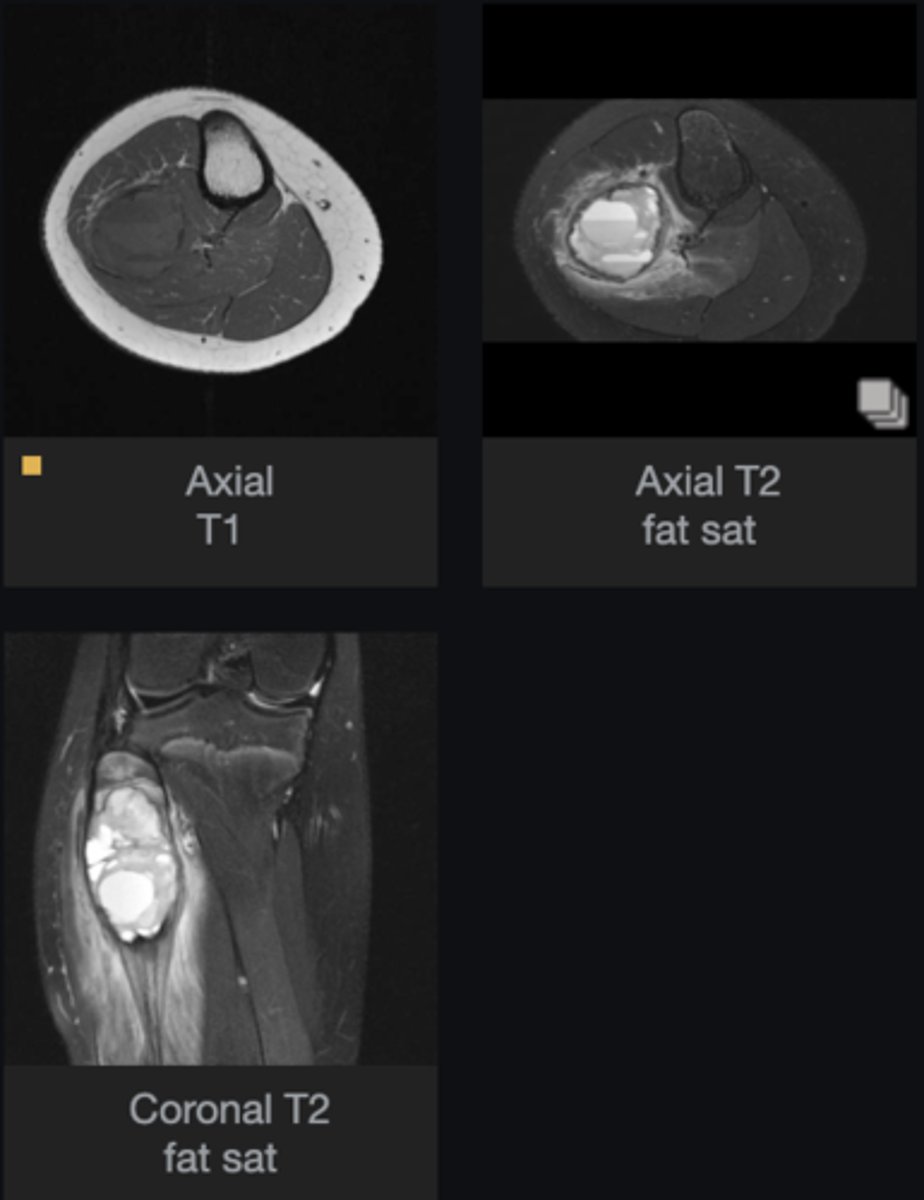

- Fluid-Fluid Levels

- Aneurysmal bone cyst

- Are there any features that help you diagnose this lesion?

- What is the most likely diagnosis?

<p>- Are there any features that help you diagnose this lesion?</p><p>- What is the most likely diagnosis?</p>